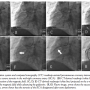

Incorporating CT images into the Navigant software and creating roadmaps have been described in a previous study.14 In brief, CT images were imported into the Navigant workstation (Figure 1A), after which the main branches of the coronary arteries were extracted and reconstructed (Figures 1B and 1C). Meanwhile, two diagnostic cines of the target vessel at least 30° apart were chosen and transferred into Navigant. The datasets were aligned by landmark registration, whereby an intrinsic fiducial vessel marker was selected on two diagnostic cines of the target vessel, after which the same landmark was identified and selected from the CT image, and then the software automatically aligned the x-ray and CT images by aligning the selected landmarks. Manual alignment was allowed if necessary. Finally, the reconstructed CT vessel was transferred onto the live fluoroscopic screen as a roadmap, and the magnetic vector could be changed

on the touch screen at the table side referring the route of the roadmap (Figure 2).